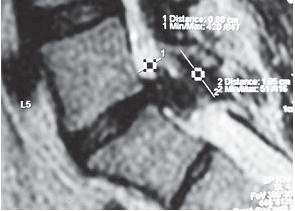

На МРТ № 21 наблюдается секвестрированная грыжа межпозвонкового диска шейного отдела позвоночника в сегменте CIII-CIV. На данном снимке, хорошо видно, как фрагмент (секвестр) грыжи межпозвонкового диска, исходя из сегмента СIII-СIV, уходит краниально (т. е. вверх, по направлению к голове) и грубо сдавливает спинной мозг на данном уровне. МРТ № 22 ![]() МРТ № 23 ![]() На МРТ № 22 и МРТ № 23 наблюдаются дорсальные грыжи межпозвонковых дисков в грудном отделе позвоночника Считается, что грыжи межпозвонкового диска больших размеров, а тем более секвестрированные грыжи, способны в значительной степени инвалидизировать человека, так как могут частично или же полностью компримировать (лат. comprimere — сжимать, сдавить) спинной мозг и его корешки. Это, несомненно, так. На практике грыжи межпозвонковых дисков, даже небольших размеров, в условиях стеноза (греч. steosis — сужение) спинномозгового канала или же фораминальной локализации (направленные в межпозвонковое отверстие) могут вызвать такие же осложнения, как и секвестры. МРТ № 24